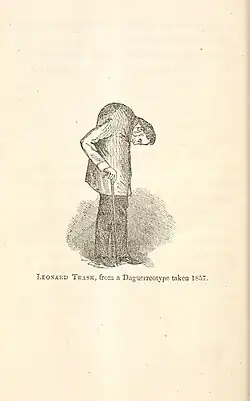

Die erste eindeutige klinische Beschreibung des typischen Krankheitsbildes der Spondylitis ankylosans gab Benjamin Collins Brodie 1850 im vierten Abschnitt („über einige Krankheitsfälle, welche mit Karies der Wirbelsäule verwechselt werden können“) des zwölften Kapitels seiner in fünfter Auflage erschienenen Schrift Pathological and Surgical Oberservations on the Diseases of the Joints.[40] Im Jahr 1858 veröffentlichte David Tucker eine Broschüre, in der er den Fall eines Patienten namens Leonard Trask beschreibt, der an einer schweren Missbildung der Wirbelsäule infolge von Spondylitis ankylosans litt.[41] Dies war der erste dokumentierte Fall von Spondylitis ankylosans in den USA.